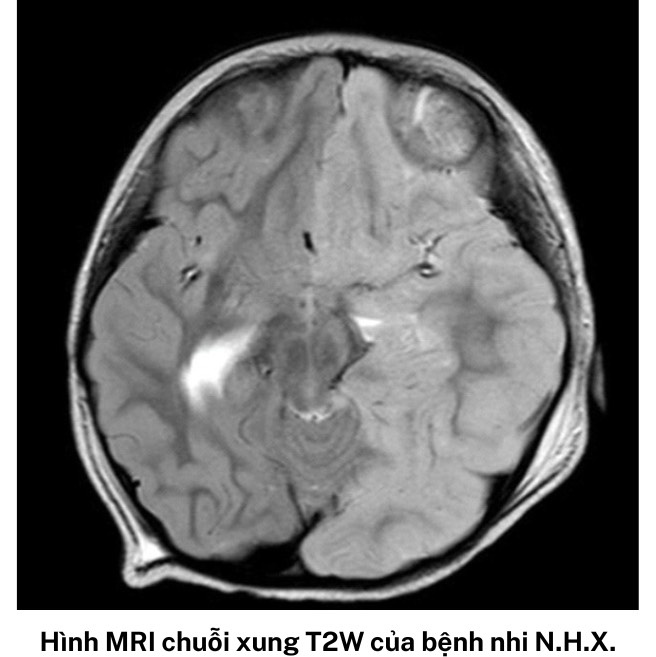

“Kết quả chụp cộng hưởng từ sọ não của bệnh nhi X. cũng cho thấy bé có tổn thương kèm phù não gần như toàn bộ nửa bán cầu trái, đẩy lệch đường giữa sang phải, bán cầu não phải bị ép xẹp", bác sĩ Việt chia sẻ.

Não bệnh nhi X. có tổn thương nhiều ở bán cầu não trái. Ảnh: BVCC.

HHE có thể được chẩn đoán dựa vào hình ảnh học não đặc trưng trên máy chụp cộng hưởng từ. Trong giai đoạn cấp tính, bệnh gây ra tổn thương phù nề nửa bán cầu não, tiếp đến là teo não không tương quan với bất kỳ vùng mạch máu nào.